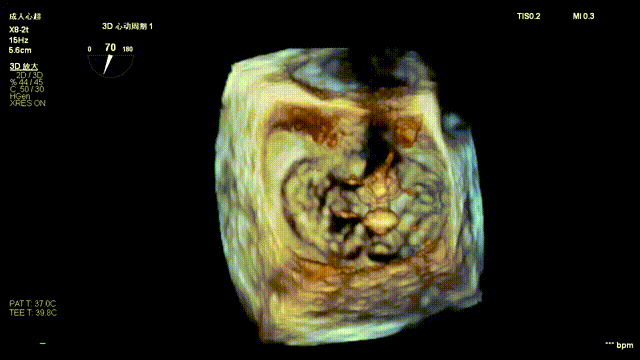

The operation was performed in a hybrid operating room and completed under the guidance of real-time three-dimensional transesophageal echocardiography (3D TEE) and X-ray fluoroscopy throughout the entire process.

Tricuspid Valve Annuloplasty Stage:Subsequently, via the right internal jugular vein approach, the K-clip® transcatheter tricuspid valve annuloplasty system was delivered to the right atrium. With the assistance of three-dimensional ultrasound stereoscopic views, a 12T clip was successfully implanted at the posteroseptal commissural annulus of the tricuspid valve, and a 14T clip at the anteroposterior commissural annulus, achieving effective constriction of the dilated annulus. Immediate postoperative assessment demonstrated that tricuspid regurgitation was improved from severe (4+) to mild (1+) instantaneously.

5.Perform the same procedure for the second clip; the clip morphology is stable under 3D imaging

Annuloplasty Effect: The tricuspid valve annulus area was reduced from 9.96 cm² to 4.6 cm², representing a 53% decrease in annulus area.

Surgical Outcome: Severe tricuspid regurgitation (4+) was reduced to mild tricuspid regurgitation (1+).